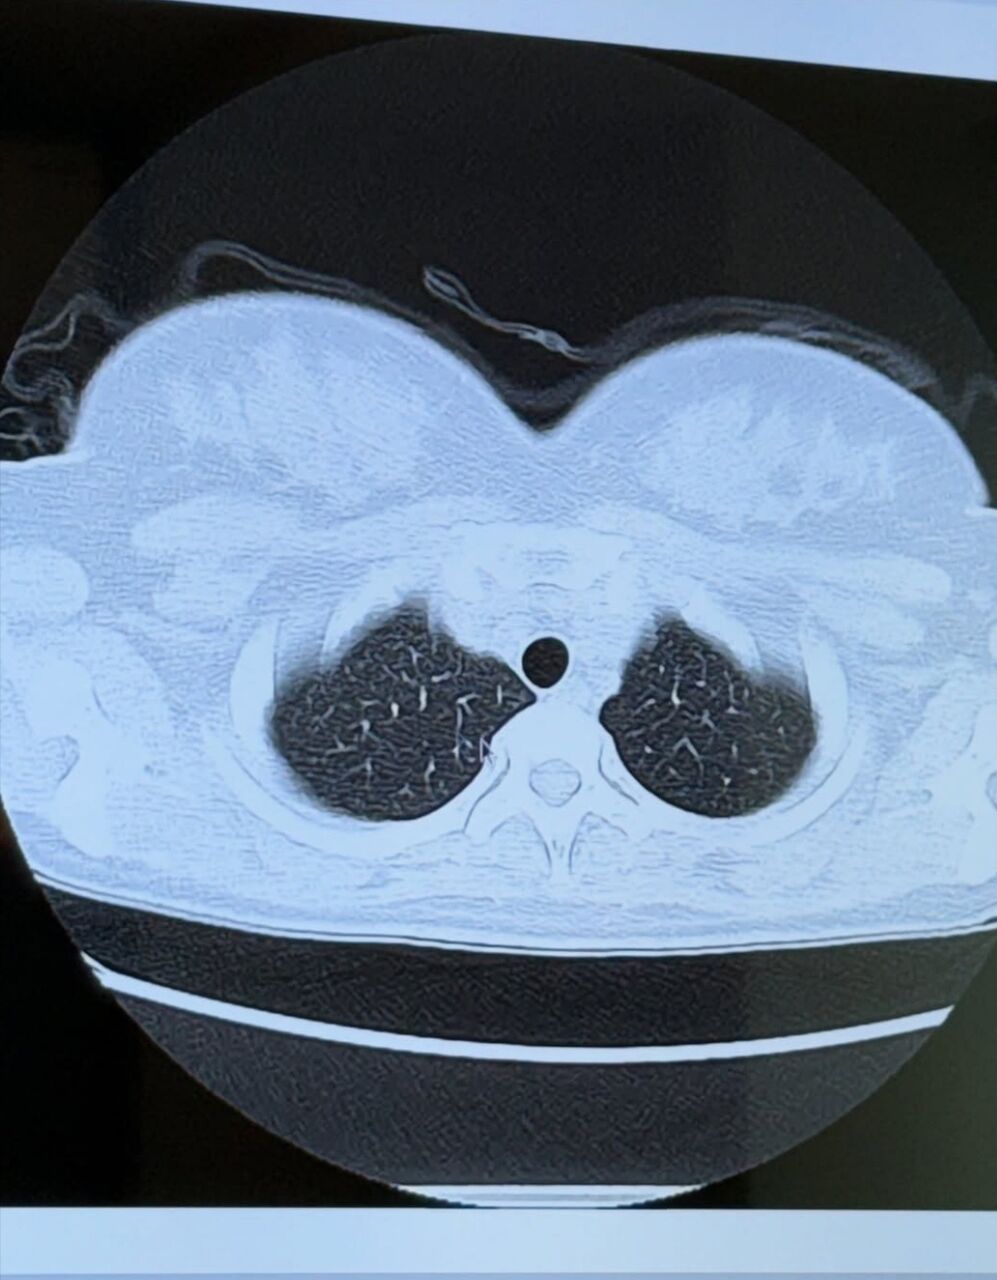

天木は「25歳ぶりに人間ドック 今年は肺のCTを撮った時の写真をお見せします!肺の上にぷるるんと天乳が見えますね」と胸部のエックス線写真を公開し「お腹減ってお胸は減らない 完璧です」とつづった。